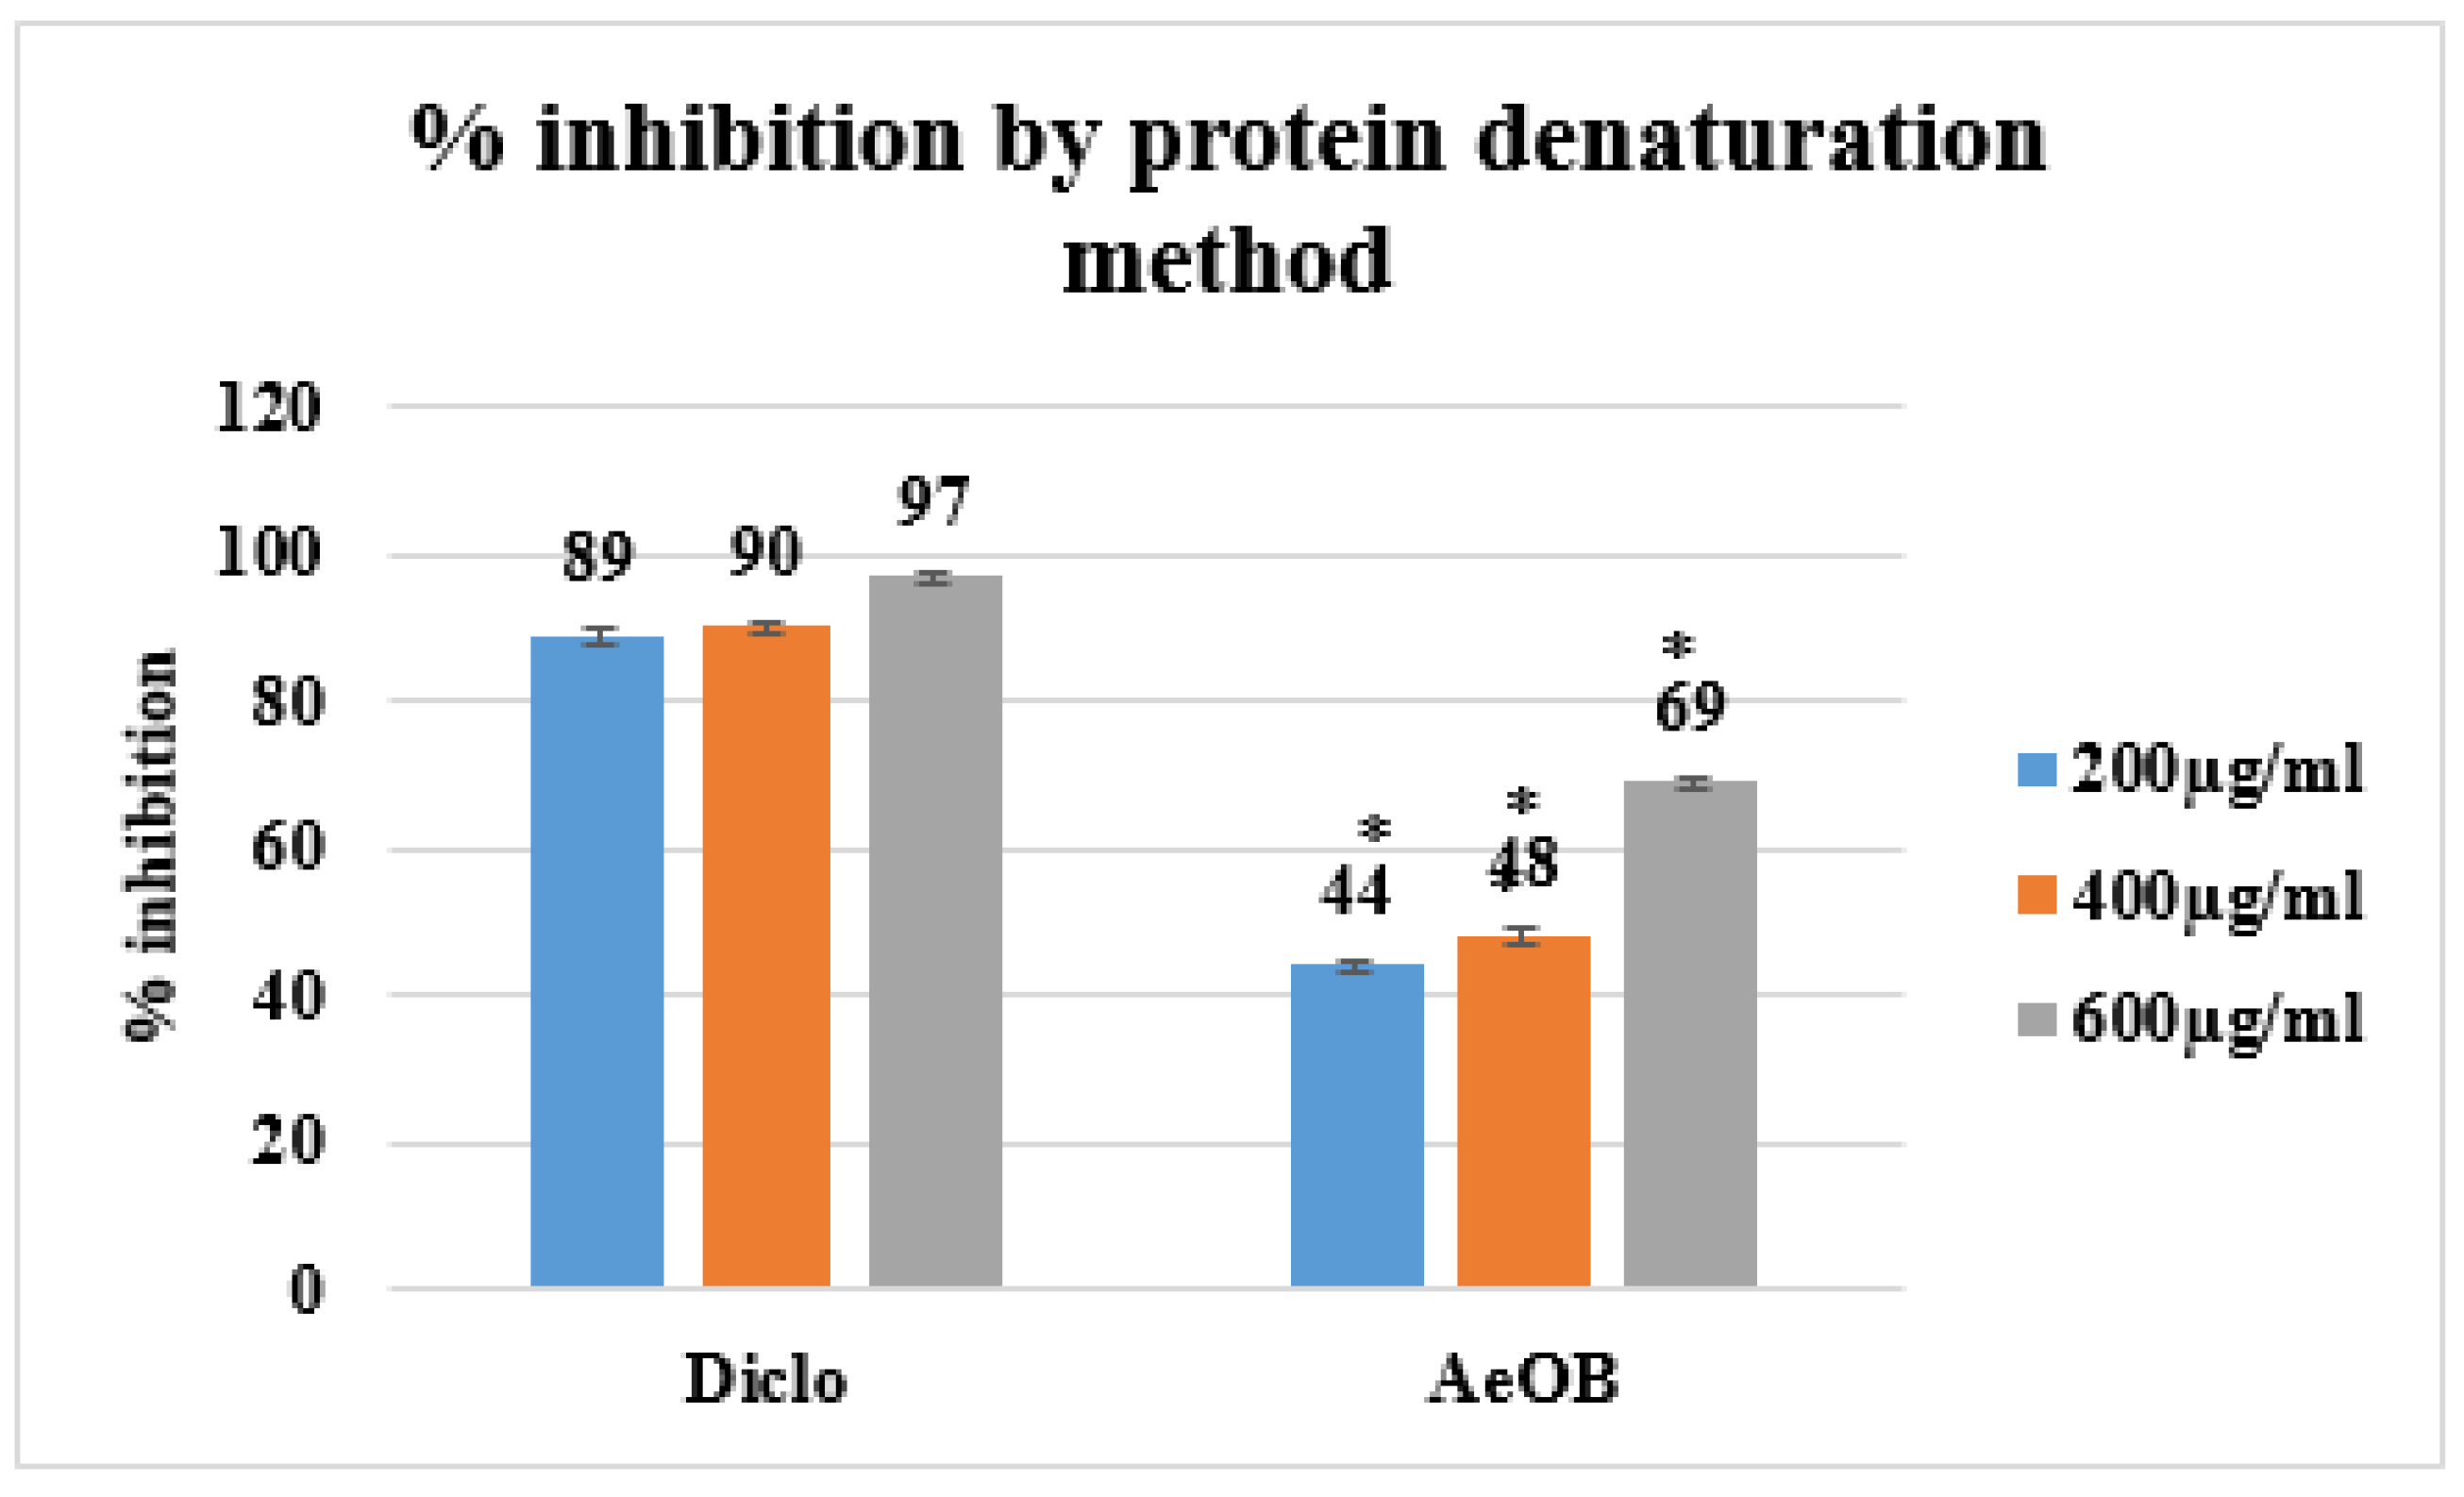

2.5.3. Egg Albumin Denaturation Method

4.7.3. Egg Albumin Denaturation Method